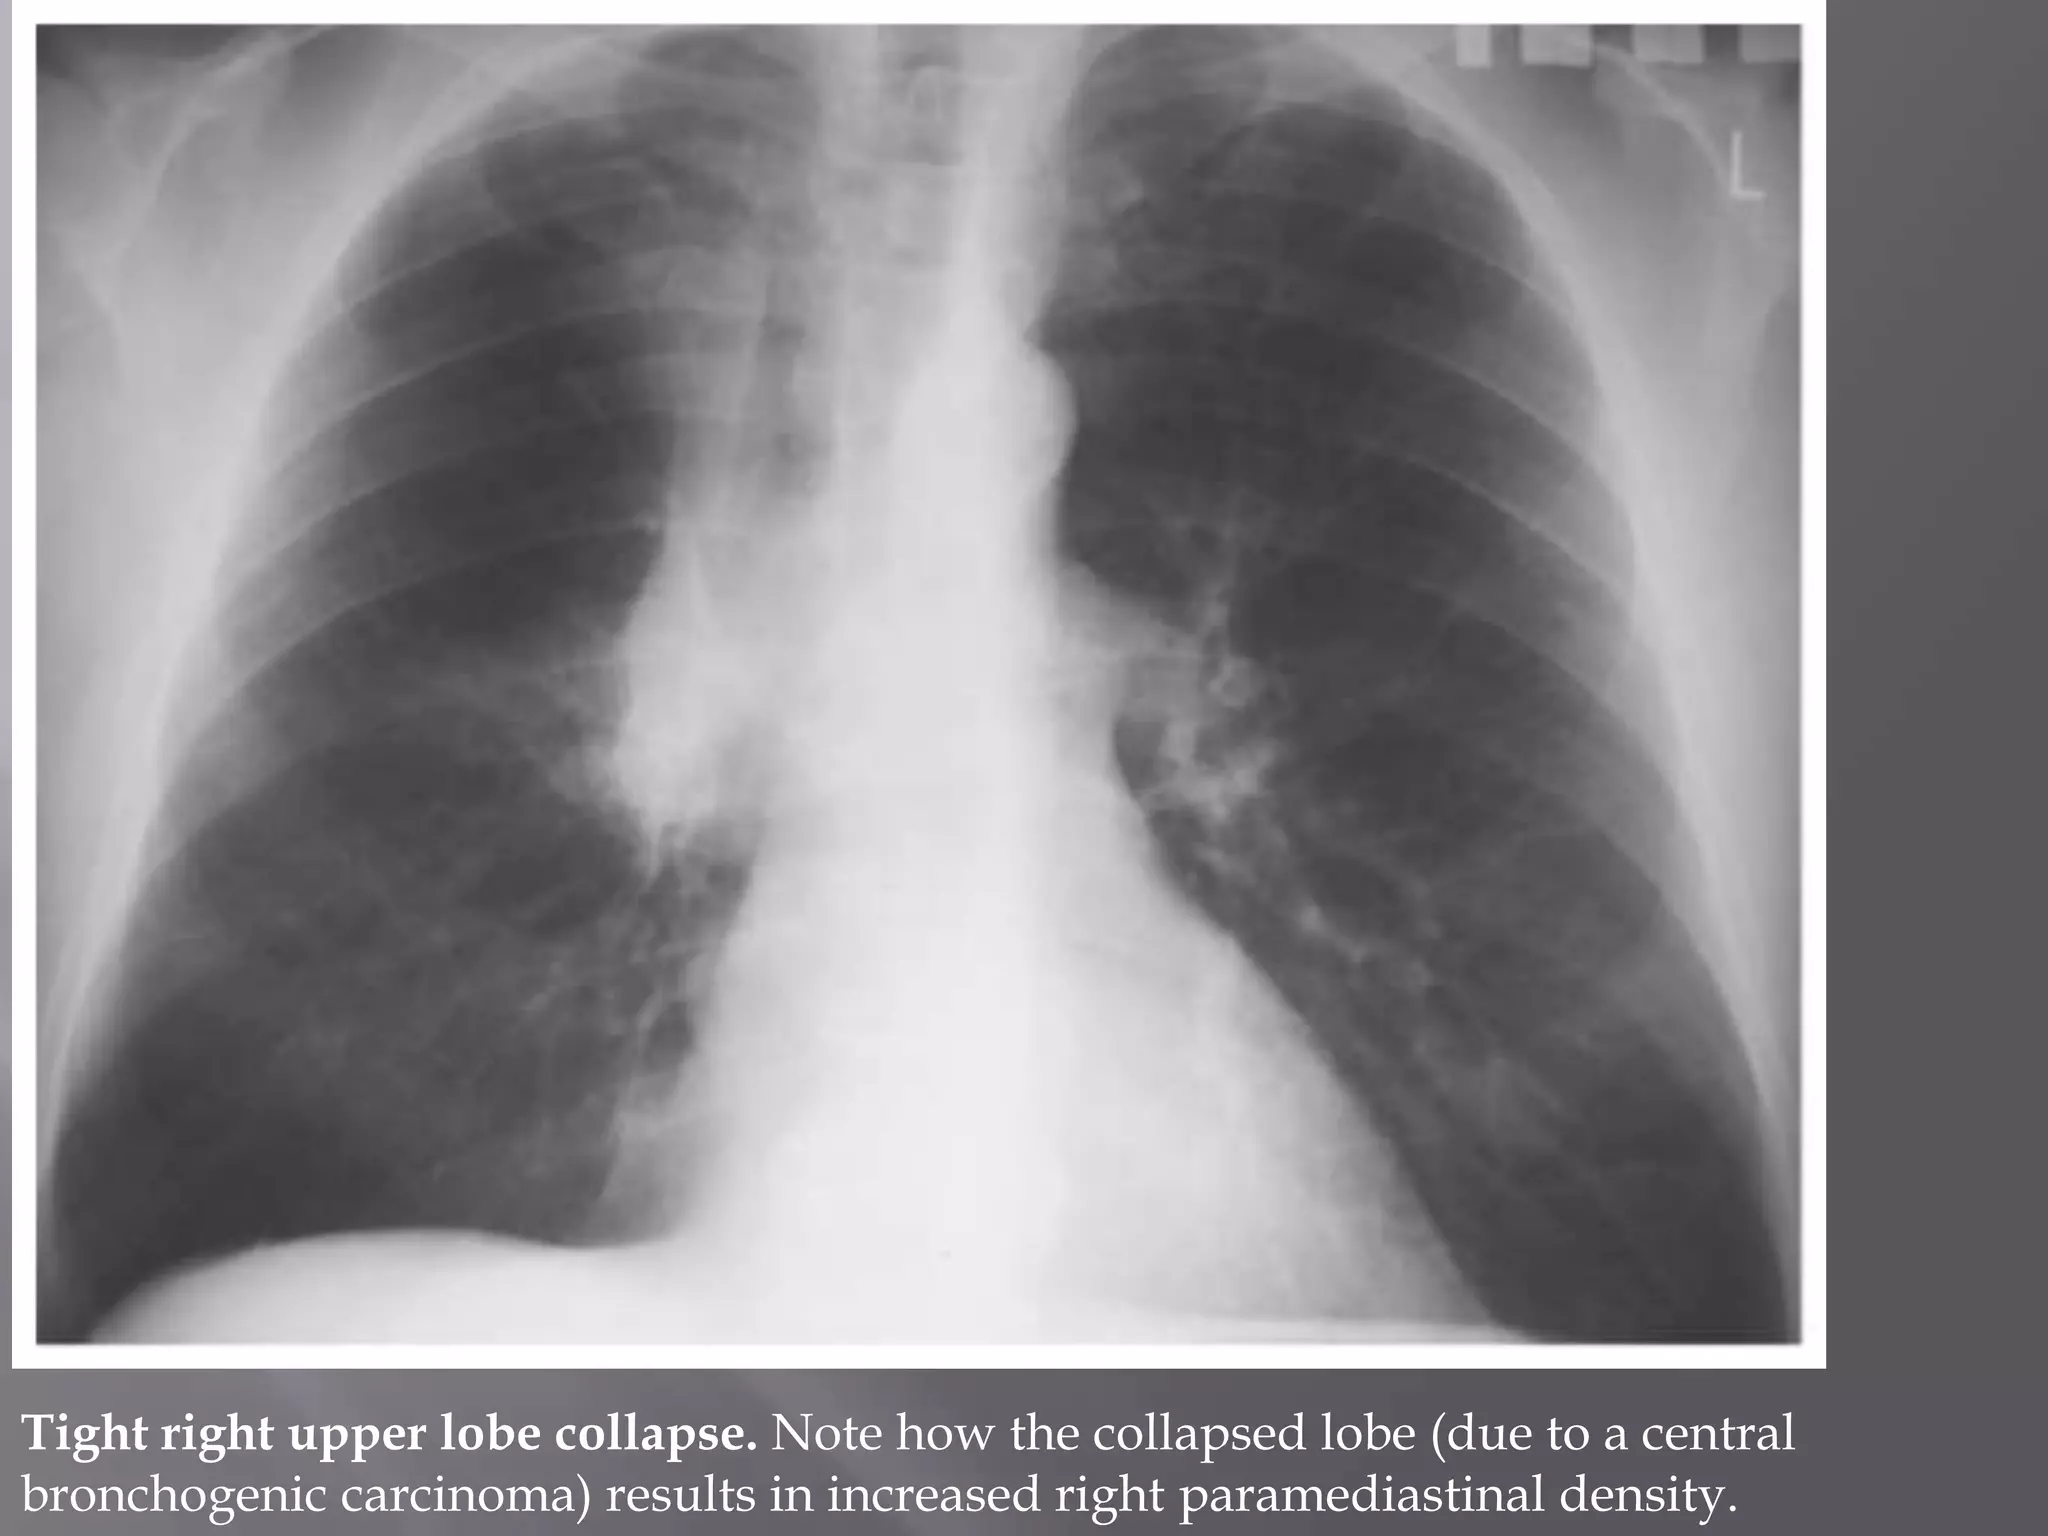

Tight right upper lobe collapse. Note how the collapsed lobe (due to a central

bronchogenic carcinoma) results in increased right paramediastinal density.

Tight right upperlobe collapse. Note how the collapsed lobe (due to a central bronchogenic carcinoma) results in increased right paramediastinal density.